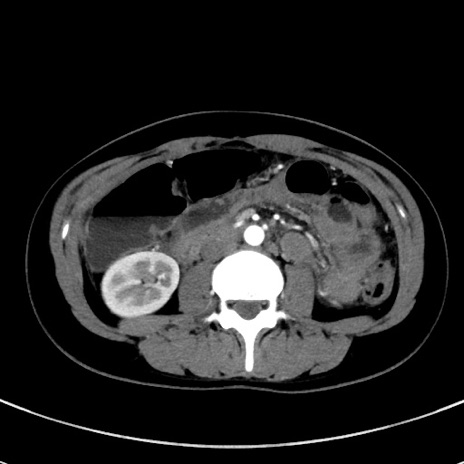

症例17(横断像)

【症例】20歳代女性

【主訴】嘔吐、下腹部痛

【現病歴】昨日夕食後に嘔吐し下腹部痛が出現。本日になっても嘔吐持続し改善しないため来院。

【身体所見】意識清明、BT 37.2℃、BP 108/67mmHg、腹部:平坦、やや硬、下腹部正中から右にかけて圧痛あり、反跳痛軽度あり、tapping pain(+)。

【データ】WBC 13600、CRP 14.94